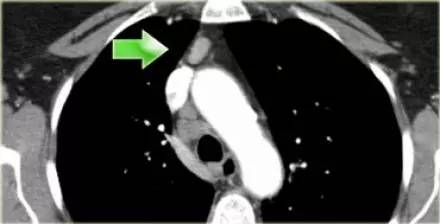

肺 CT 横断面上的血管前淋巴结(3A)